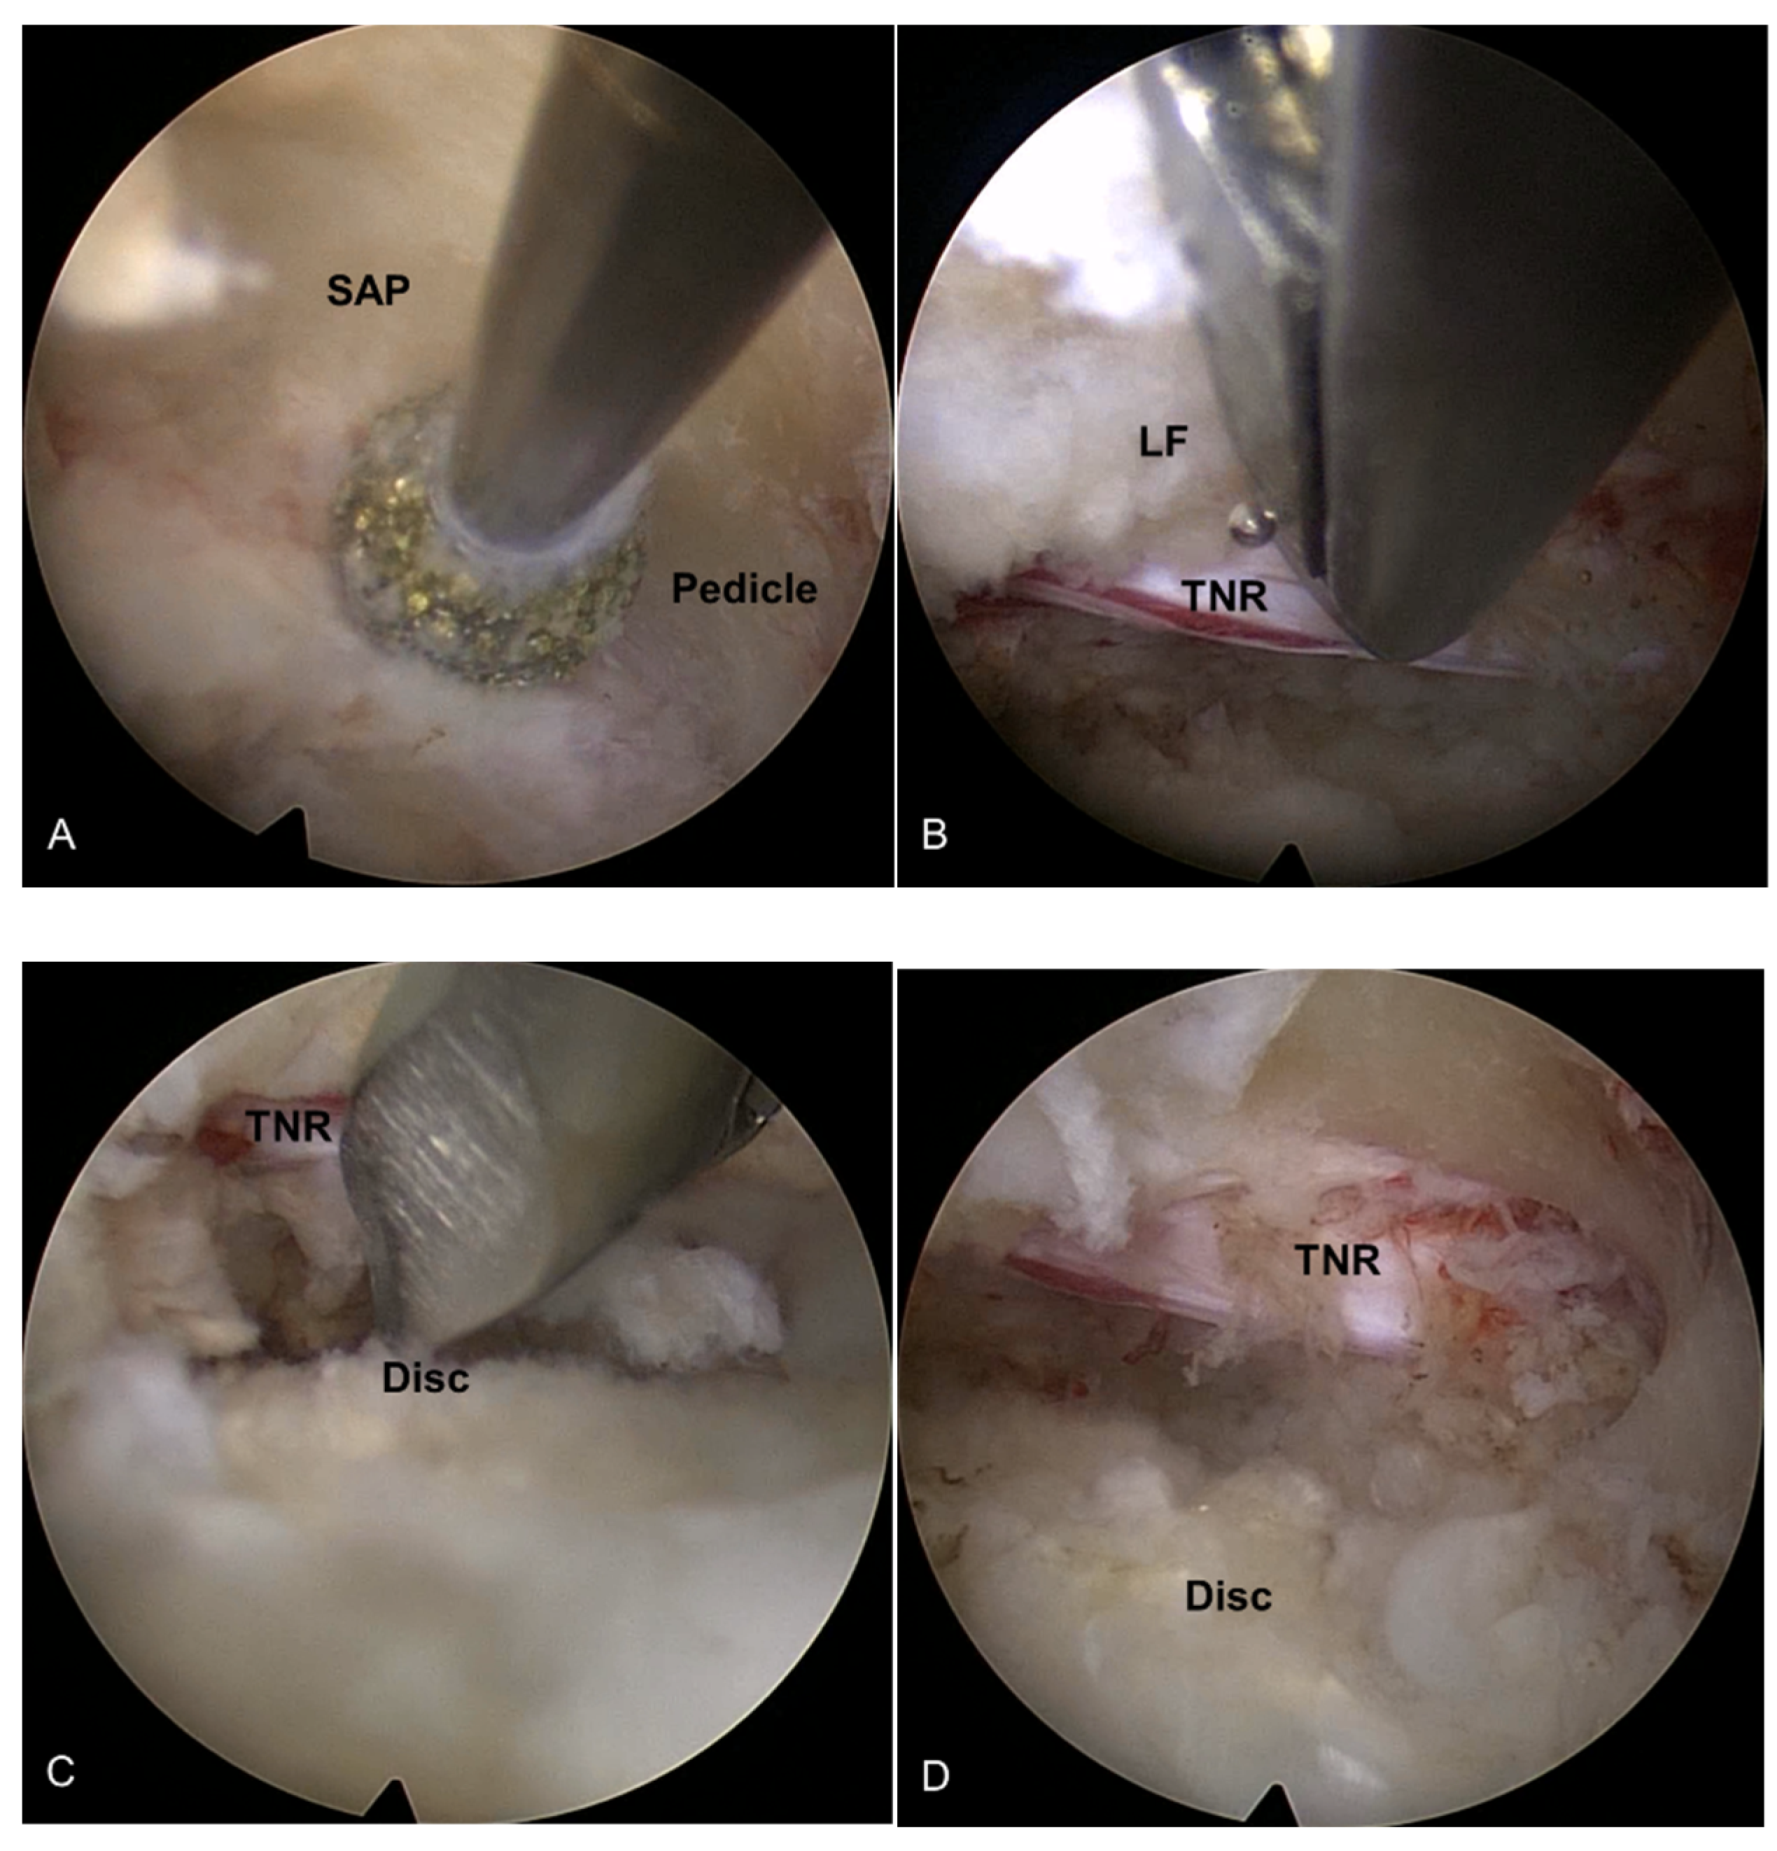

Figure 3.

An illustrative case of an 81-year-old female patient treated with TELLRD. (A) Preoperative axial CT showing central and lateral recess stenosis at the L3–L4 level (arrows). (B) Postoperative axial CT showing lateral spinal canal decompression following undercutting of the hypertrophic SAP and LF compressing the TNR (arrowheads). (C) Preoperative sagittal CT showing lateral recess stenosis at the L3–L4 level (arrows). (D) Postoperative sagittal CT showing lateral spinal canal decompression following undercutting of the hypertrophic SAP and LF compressing the TNR (arrowheads). (E) Postoperative coronal CT showing lateral recess stenosis at the L3–L4 level (arrows). (F) Postoperative coronal CT showing lateral spinal canal decompression following undercutting the SAP and LF compressing the TNR (arrowheads). TELLRD, transforaminal endoscopic lumbar lateral recess decompression; SAP, superior articular process; LF, ligamentum flavum; TNR, traversing nerve root.